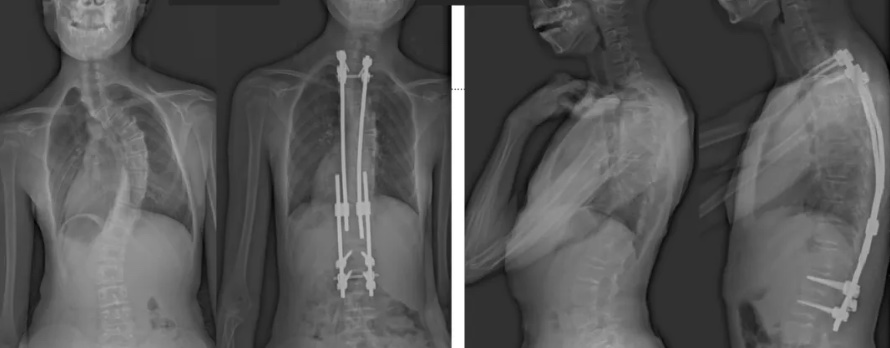

術(shù)后第二天,白瑪就下地活動(dòng)了。媽媽驚喜地發(fā)現(xiàn),白瑪一下子“長(zhǎng)高”了近十厘米,重新抬起了頭,挺直了脊梁,肩膀也不歪了,可謂“脫胎換骨”。媽媽激動(dòng)地錄制了一段白瑪走路的身影,把喜悅分享給全家。白瑪?shù)男g(shù)后檢查也提示,手術(shù)成功,恢復(fù)良好。

白瑪?shù)恼恍g(shù)前、術(shù)后對(duì)比圖(左側(cè));側(cè)位術(shù)前、術(shù)后對(duì)比圖(右側(cè))